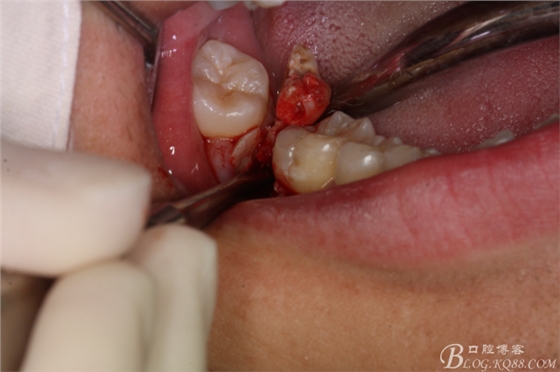

圖7.不切開(kāi)、不翻瓣、利用有限空間直接高速牙鉆分牙

圖8.先橫斷47牙冠,盡量從牙頸部橫斷

圖9.潛掘法橫斷牙冠